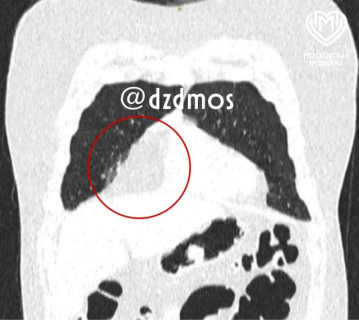

Мальчик жаловался на периодические боли в груди, одышку и синеву над верхней губой. Родители школьника обратились в поликлинику, где на рентгенографии врачи обнаружили патологическую тень в передней части грудной клетки.  Компьютерная томография подтвердила наличие крупного образования размером 17 на 6 см.

«Жировые образования встречаются чаще у взрослых и реже у детей с избыточным весом. Наш пациент страдал ожирением II степени. В его случае новообразование срослось с перикардом (сердечной сумкой) и диафрагмой, сместило сердце влево и еще поджимало правое легкое, поэтому мальчик чувствовал себя плохо.